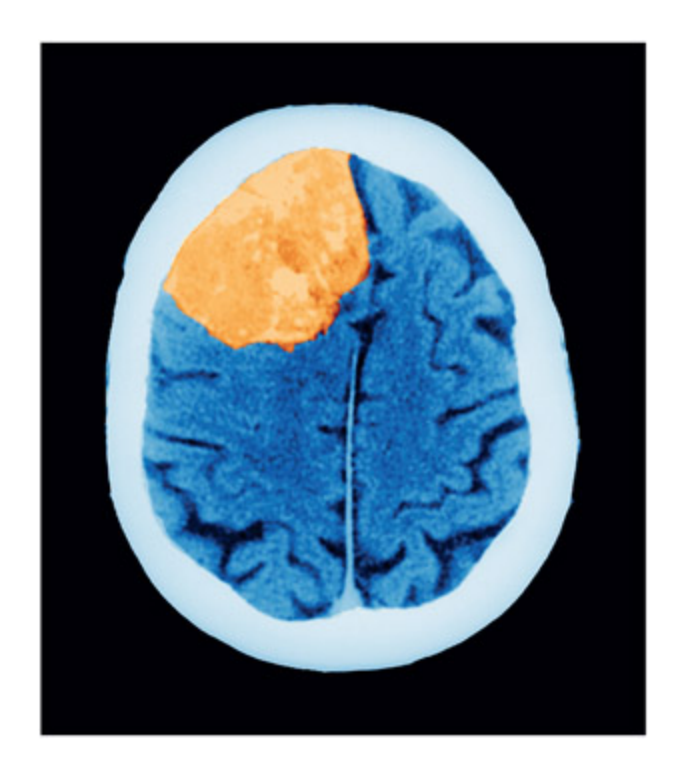

뇌는 자궁 다음으로 종양이 흔한 부위이며, 수막종(meningioma)과 신경교종(glioma) 같은 원발성 종양과 다른 부위에서 전이된 전이성 종양으로 구분된다. 종양은 비정상적 세포 증식으로 인해 신경세포에 압력을 가하여 기능 장애나 세포 사멸을 유발한다.

e brain is the second most common site for tumors (aer the uterus), and brain tumors are oen spread from other parts of the body (these are called metastatic tumors). Tumors are caused when new cells are produced in a poorly regulated manner. Brain tumors are formed from supporting cells su as the meninges and glia (termed “meningioma” and “gliomas,” respectively). Tumors adversely affect the functioning of the brain because the extra cellular material puts pressure on the neurons, disrupting functioning and possibly leading to cell death.

📊 그림 설명

CT 스캔에서 관찰되는 뇌종양의 영상이다. 종양이 주변 뇌 조직을 압박하여 뇌의 형태가 왜곡되어 있으며, 이로 인해 손상 범위를 정확히 추정하기 어렵고 표준 뇌 지도에 매핑하기 곤란함을 보여준다. 이는 종양 환자의 손상-결함 분석에서 구조적 영상 기술의 한계를 시각적으로 예시한다.

A tumor (here shown on a CT scan) can make it hard to estimate lesion size, and the distortion in the shape of the brain makes it hard to map onto a standard atlas. Sovereign, ISM/Science Photo Library.